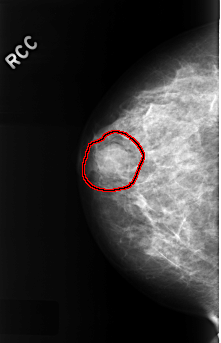

ics_version 1.0 filename C-0333-1 DATE_OF_STUDY 22 12 1995 PATIENT_AGE 44 FILM FILM_TYPE REGULAR DENSITY 2 DATE_DIGITIZED 12 10 1998 DIGITIZER LUMISYS LASER SEQUENCE LEFT_CC LINES 4480 PIXELS_PER_LINE 2904 BITS_PER_PIXEL 12 RESOLUTION 50 NON_OVERLAY LEFT_MLO LINES 4368 PIXELS_PER_LINE 2856 BITS_PER_PIXEL 12 RESOLUTION 50 NON_OVERLAY RIGHT_CC LINES 4456 PIXELS_PER_LINE 2864 BITS_PER_PIXEL 12 RESOLUTION 50 OVERLAY RIGHT_MLO LINES 4424 PIXELS_PER_LINE 2864 BITS_PER_PIXEL 12 RESOLUTION 50 OVERLAY |

FILE: C_0333_1.RIGHT_CC.OVERLAY TOTAL_ABNORMALITIES 1 ABNORMALITY 1 LESION_TYPE MASS SHAPE OVAL MARGINS CIRCUMSCRIBED ASSESSMENT 4 SUBTLETY 4 PATHOLOGY BENIGN TOTAL_OUTLINES 1 BOUNDARY |